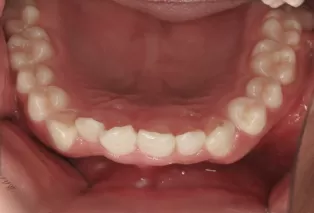

Intraoral photos after treatment